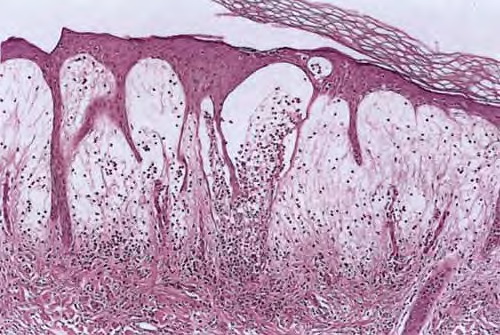

Branchial cleft cyst =كيسة الشق الغلصمي Branchial Cyst (Branchial Cleft Cyst) Sequestration of first or second branchial cleft membranes results in these cysts, sinuses, or tags. EPIDEMIOLOGY Branchial cleft cysts are largely sporadic, but autosomal dominant cases have been reported. There is no gender predominance. Ten percent of lesions are bilateral. ETIOLOGY AND […]